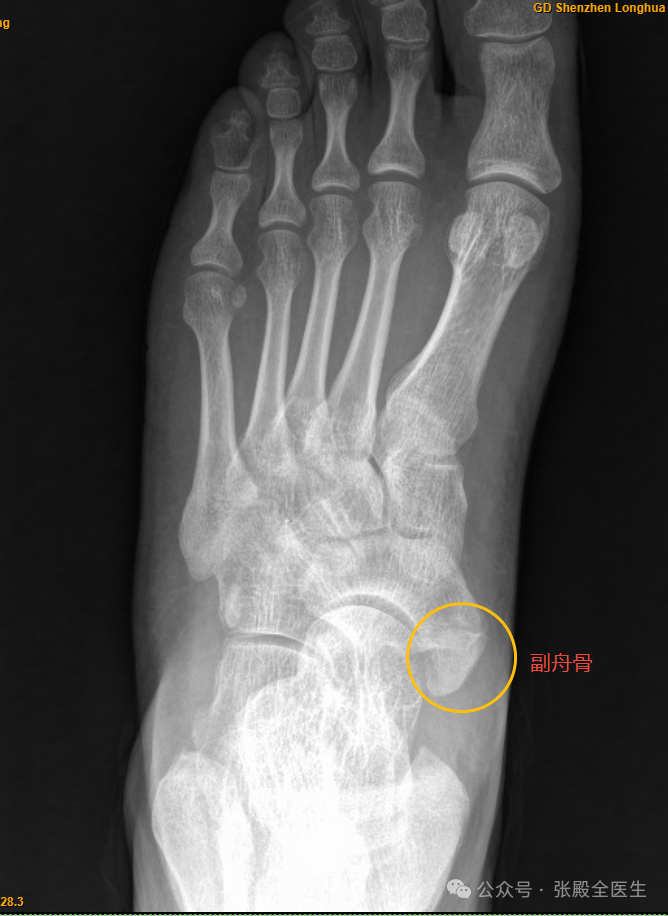

患者XX,男,35岁,左足疼痛不适半年。患者无诱因出现左足疼痛,受凉后明显,连及小腿,无力感。平素口干、口苦,时大便稀,睡眠差,诉经常喝可乐。查足X片提示:左足副舟骨。左足跟骨质增生。化验尿酸:451μmol/l。这位患者足痛部位为足背及脚趾,考虑主要为痛风性关节炎,非副舟骨导致。

副舟骨(Accessory Navicular Bone)是一个先天性骨变异,主要位于内侧舟骨的后方,通常被认为是一种附加骨。并不是每个人都有这种骨骼,大约5%到15%的人群可能会存在副舟骨。对于大多数人来说,副舟骨不会引起任何问题,但在一些情况下,它可能会导致疼痛和其他不适症状。副舟骨的分型通常依据其形态和与舟骨的连接方式进行分类,目前最广泛使用的是Geist分型,分为三种类型: